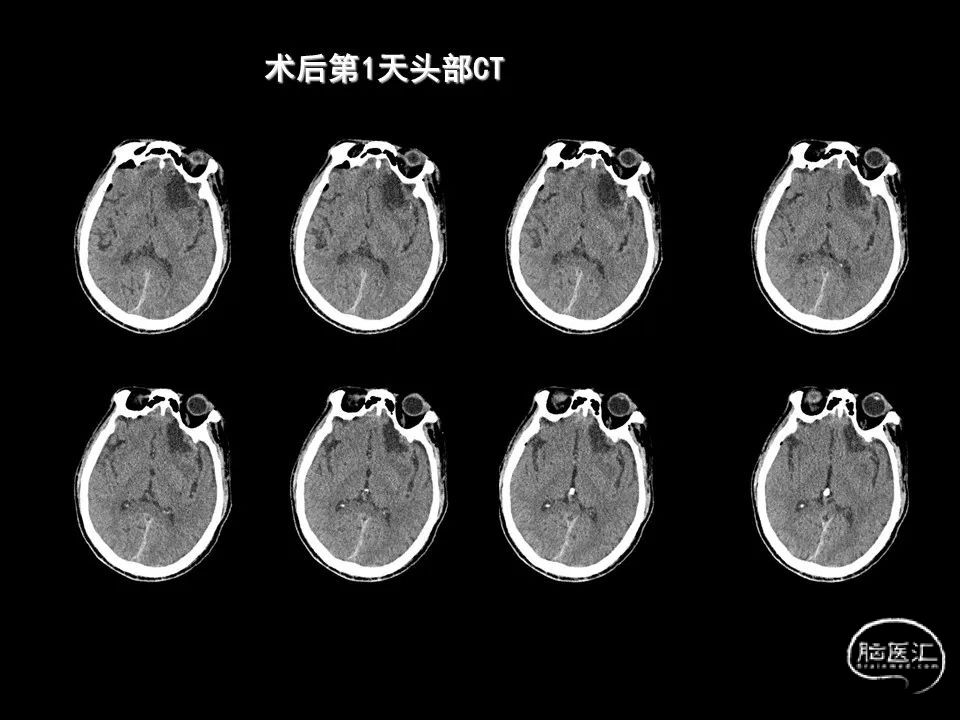

今天为大家分享的是《监测有道丨颅脑创伤-神经重症周刊》第338期,由海南省人民医院朱蔚林教授带来的:2例脑出血微创手术,欢迎阅读、分享。

主要从事神经内镜下垂体腺瘤、高血压脑出血手术,鞍区肿瘤,颅底肿瘤,脑膜瘤、听神经瘤、胶质瘤等显微外科手术,颅脑创伤,脑积水、蛛网膜囊肿、颅内感染等救治